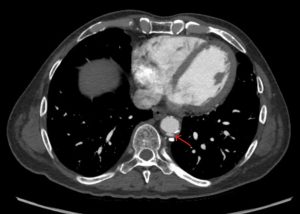

Penetrating aortic ulcers are usually an incidental finding on CT or MR. On CT look for contrast that is separate from the main aorta channel. An ulcer is sometimes hard to distinguish from an ulcerated plaque. An ulcerated plaque is actually not considered part of the “acute aortic syndrome” spectrum (it is more in line with a “regular” atherosclerotic process. I recommend reviewing images with vascular radiology. Doing so has helped me in the past. One differentiator is if contrast goes beyond the diameter of the aorta. Contrast outside the diameter denotes an ulcer (so, yes, the example in the picture below is not a perfect one):